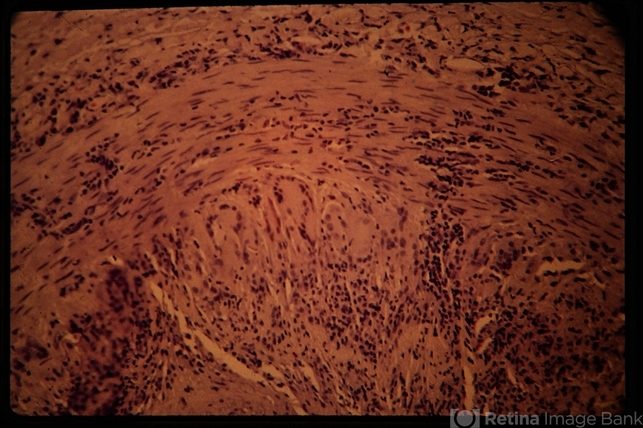

- Temporal artery biopsy specimen showing multi-nucleated giant cells.